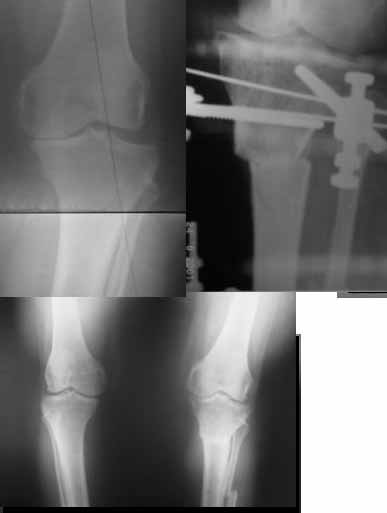

Вот ещё картинки, которые отправлял в Ортопод. Коррекция кривизны и удлинение на 3 см.

Yesterday one leg was done (my plan to make both in one session were cancelled because of external reasons). So much exciting and useful experience.

The osteotomy line i planned to make a bit oblique, but not so as you suggested. But at the moment of osteoclasis after corticotomy through the anterior stab wound the line became almost as you described. Now problem is how to reproduce thee line at the next leg ;-)

The prominent fragment seems to be useful for cosmetic purposes, because aesthetic guys perform medialization of the distal fragment to gain attractive curve at the medial side of the leg. Also all locking options became available - initially i planned to engage only two most

proximal 45 degree holes.

I cut the fibula because i externally rotated the distal fragment by 6-7 degrees. With only angular correction it didn't show any displacement.

Today CT for estimation of rotation was performed, results i will see only tomorrow. Rotation of the operated limb can be corrected with the second surgery. Comments/critics are welcome.

Операция была интересной, много полезного опыта приобрел.

Снимки в приложении - фас сравнительный с неоперированной ногой. Жду критики.

Впрос про остеотомию большеберцовой непраздный. Эта получилась при надломе несколько более наклонно, чем я делал (сейчас проблема,

как на второй ноге сделать так же). Вот этот высоящий "зуб" центрального отломка не заменит ли в плане косметики то, что получается при медиализации дистального?

Nice job!

It is very interesting to me that as you have derotated the tibia you have centred the patella, I think and the prox tibia looks much more anatomic.

The analysis in the attached images is direct, just using the tools.

Tibial tilt is perhaps more than you want but the tibial correction is to 90 (very slight over

correction.

Will need full length views to tell us about the hka but it appears neutral.

Measurements took 4 mins

Derek